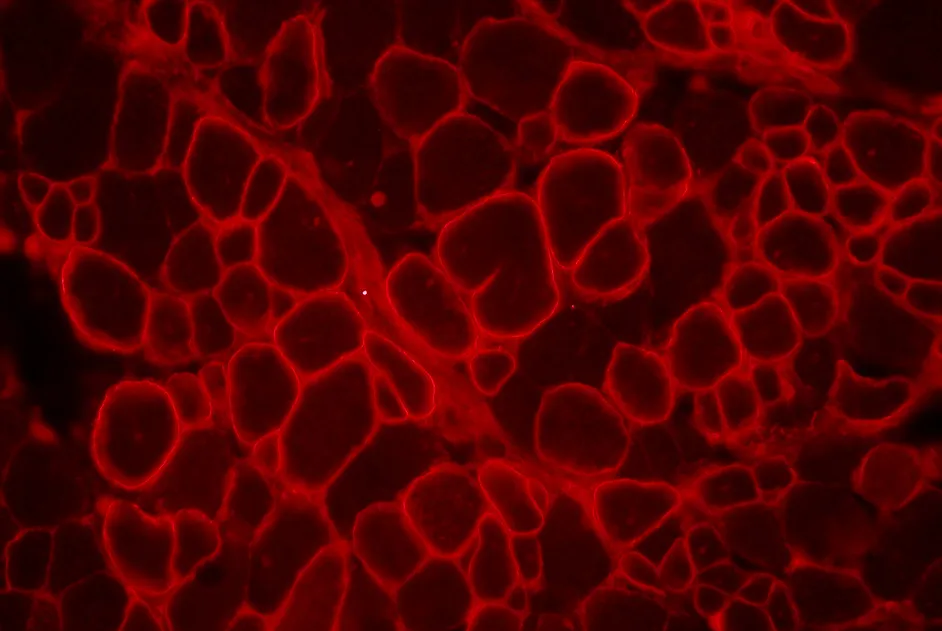

Rétablir la fonction de la dysferline mutée en la relocalisant à la membrane à l’aide de peptides dérivés de la dysferline.